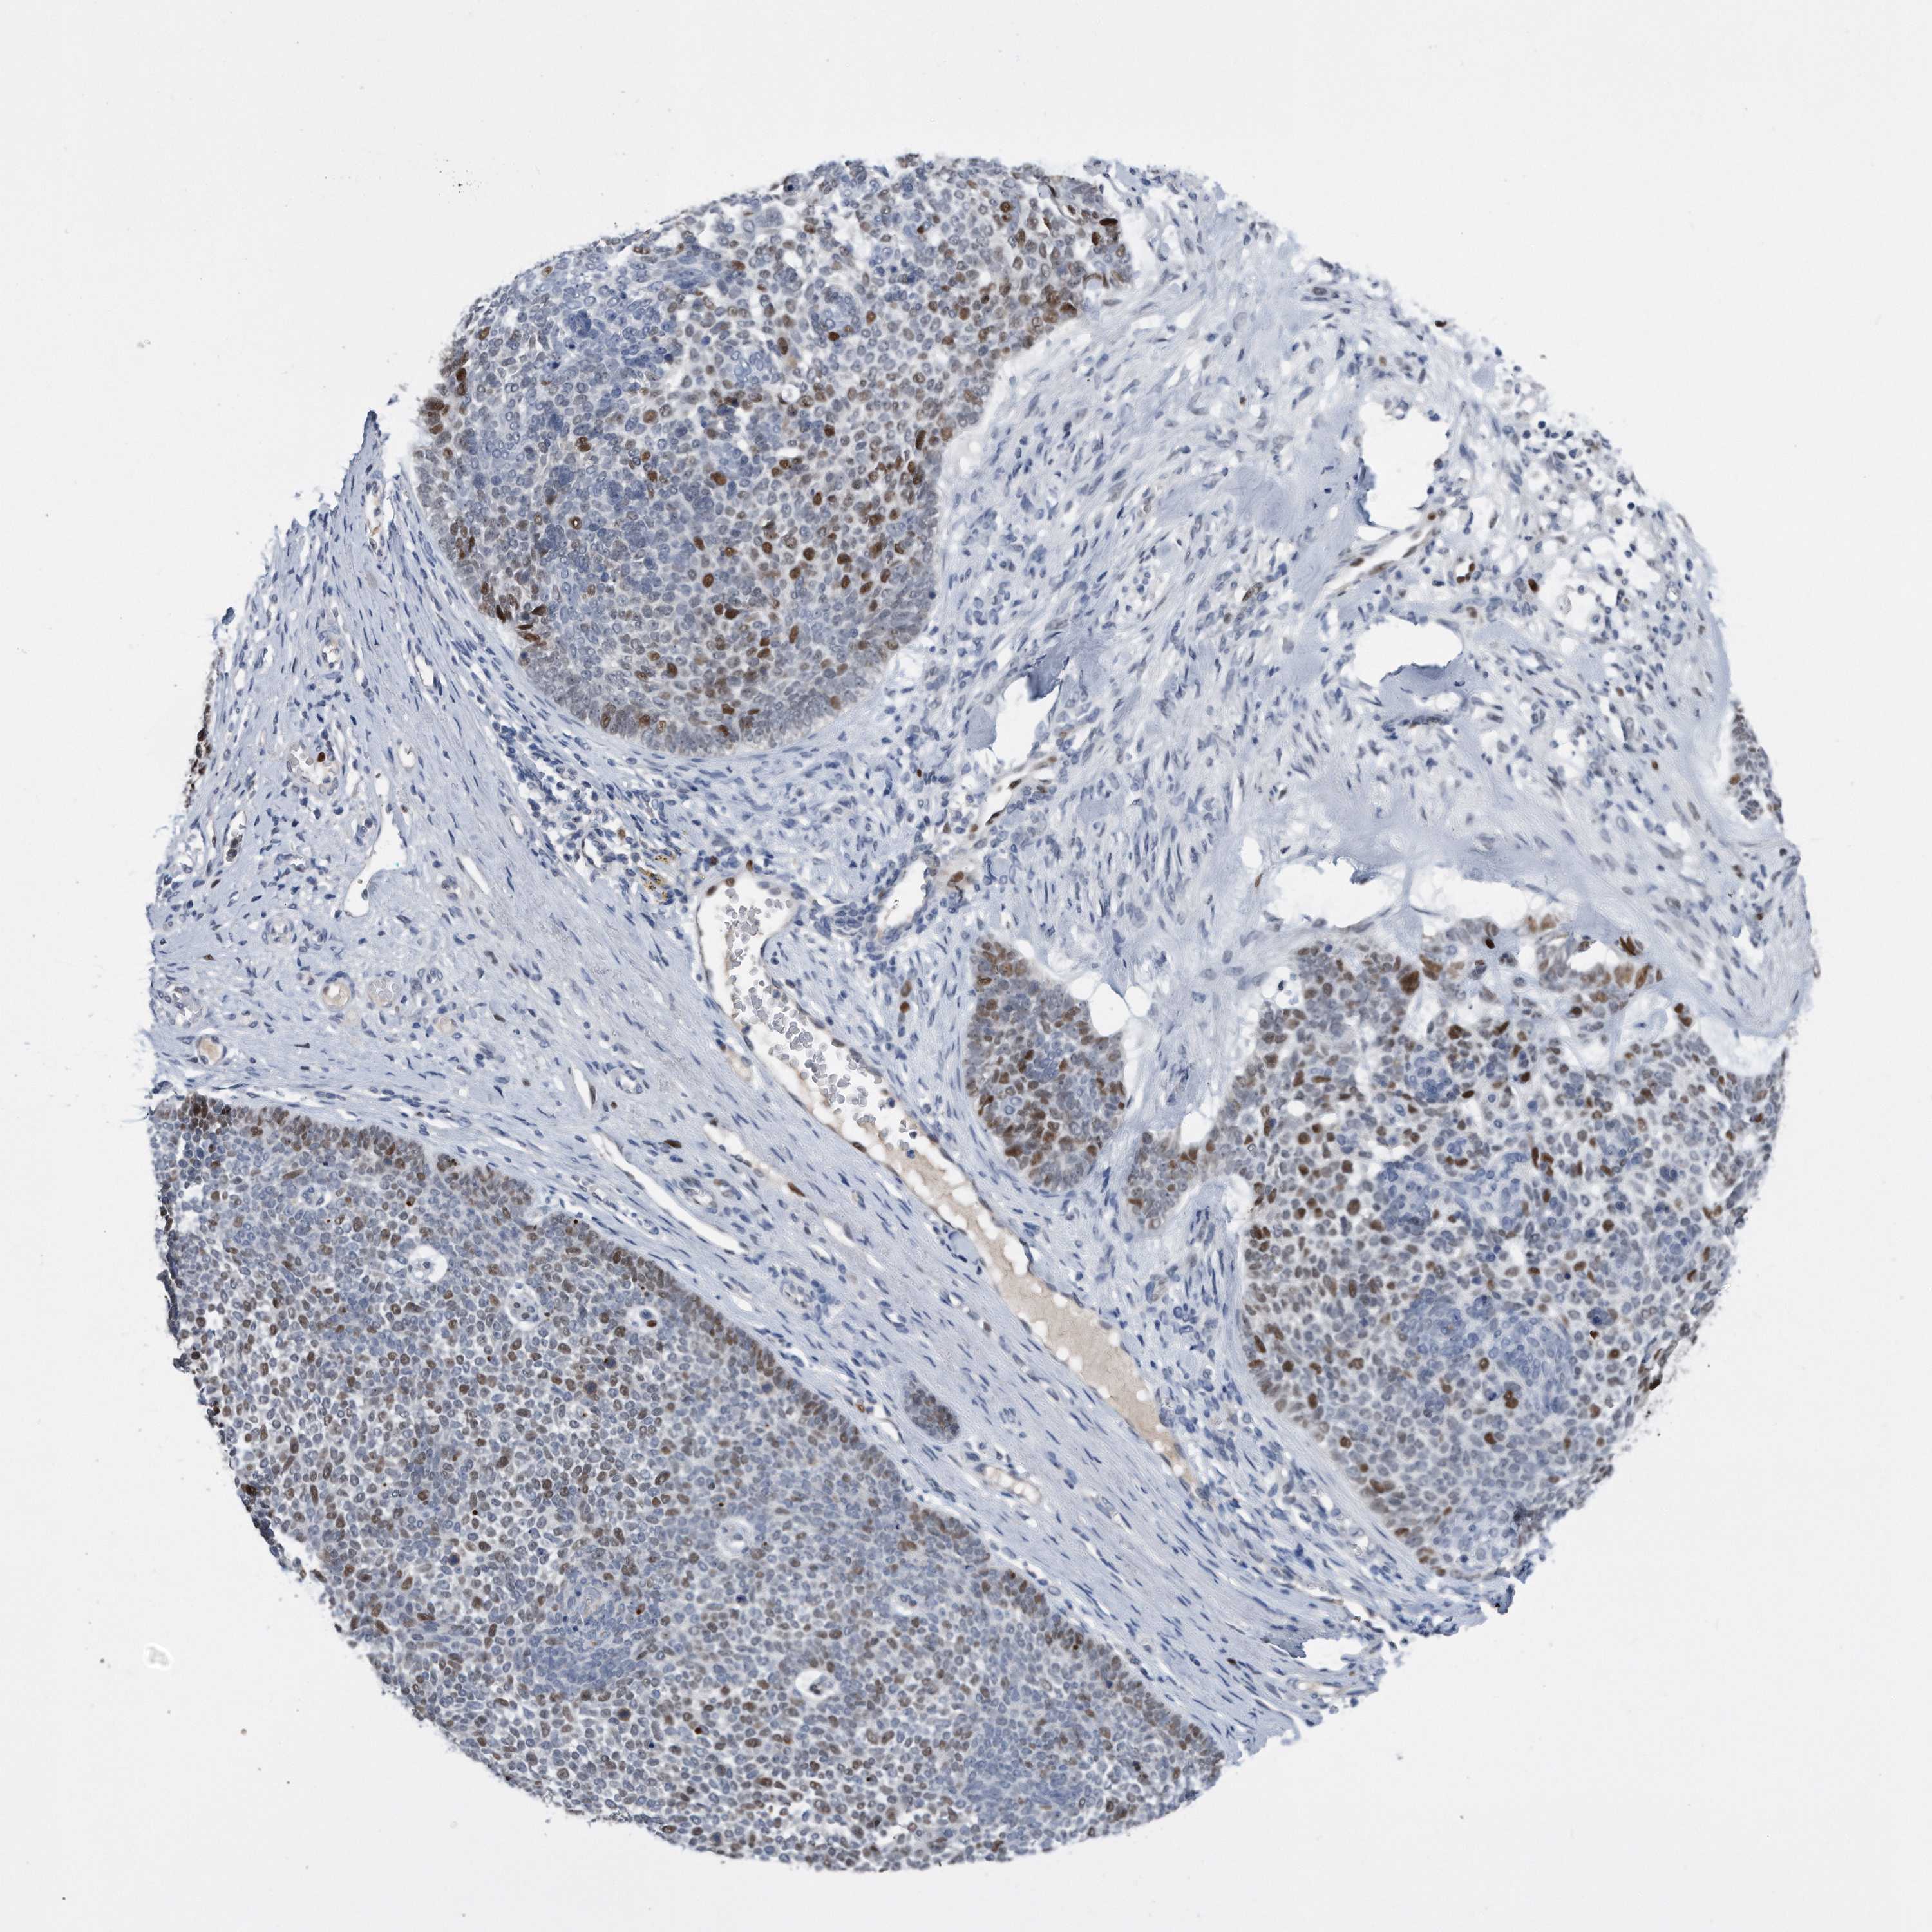

CANCER SKIN CANCER Show tissue menu

Basal cell and squamous cell cancer

SKIN CANCER - Protein expressioni

A mouse-over function shows sample information and annotation data. Click on an image to view it in a full screen mode. Samples can be filtered based on level of antibody staining by selecting one or several of the following categories: high, medium, low and not detected. The assay and annotation is described here.

Antibody stainingi

Antibody staining in the annotated cell types in the current human tissue is reported as not detected, low, medium, or high, based on conventional immunohistochemistry profiling in selected tissues. This score is based on the combination of the staining intensity and fraction of stained cells.

Each image is clickable and will lead to virtual microscopy that enables deeper exploration of all samples and also displays staining intensity scores, fraction scores and subcellular localization as well as patient and tissue information for each sample.

Basal cell carcinoma

Squamous cell carcinoma, NOS

Squamous cell carcinoma, metastatic, NOS